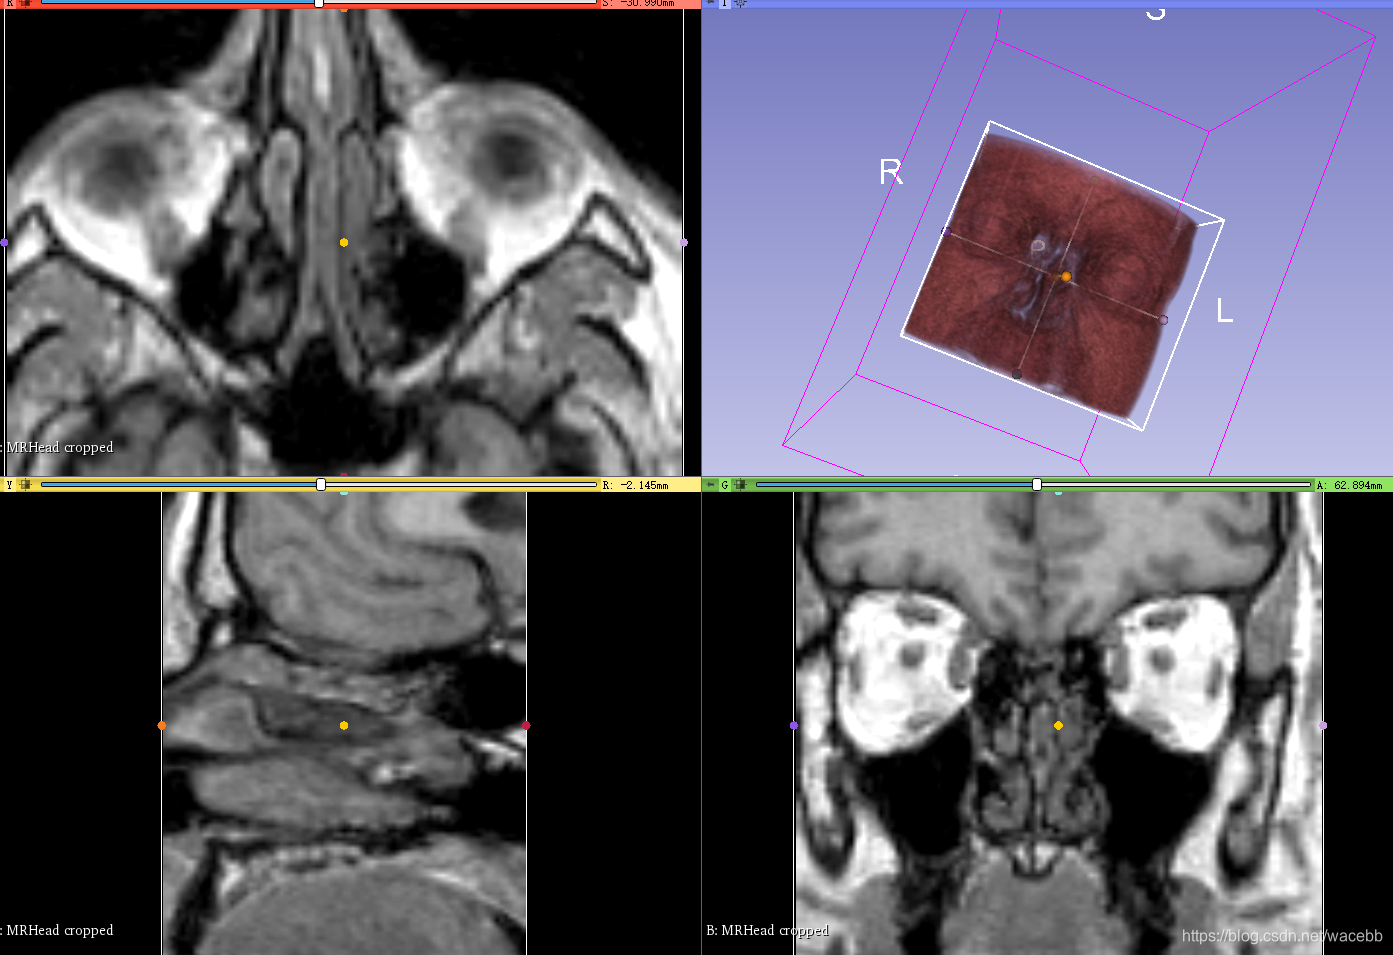

就可以创建好新的ROI,并且在右边显示:

于此同时,我们可以看到文件名称:

这样我们就创建了一个新文件:

我们可以看到input 从一个文件变成了现在的两个: